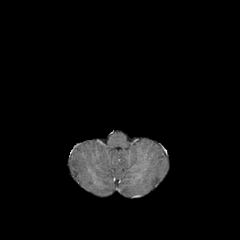

Objectives: This work aims to explore the impact of multicenter data heterogeneity on deep learning brain metastases (BM) autosegmentation performance, and assess the efficacy of an incremental transfer learning technique, namely learning without forgetting (LWF), to improve model generalizability without sharing raw data. Materials and methods: A total of six BM datasets from University Hospital Erlangen (UKER), University Hospital Zurich (USZ), Stanford, UCSF, NYU and BraTS Challenge 2023 on BM segmentation were used for this evaluation. First, the multicenter performance of a convolutional neural network (DeepMedic) for BM autosegmentation was established for exclusive single-center training and for training on pooled data, respectively. Subsequently bilateral collaboration was evaluated, where a UKER pretrained model is shared to another center for further training using transfer learning (TL) either with or without LWF. Results: For single-center training, average F1 scores of BM detection range from 0.625 (NYU) to 0.876 (UKER) on respective single-center test data. Mixed multicenter training notably improves F1 scores at Stanford and NYU, with negligible improvement at other centers. When the UKER pretrained model is applied to USZ, LWF achieves a higher average F1 score (0.839) than naive TL (0.570) and single-center training (0.688) on combined UKER and USZ test data. Naive TL improves sensitivity and contouring accuracy, but compromises precision. Conversely, LWF demonstrates commendable sensitivity, precision and contouring accuracy. When applied to Stanford, similar performance was observed. Conclusion: Data heterogeneity results in varying performance in BM autosegmentation, posing challenges to model generalizability. LWF is a promising approach to peer-to-peer privacy-preserving model training.